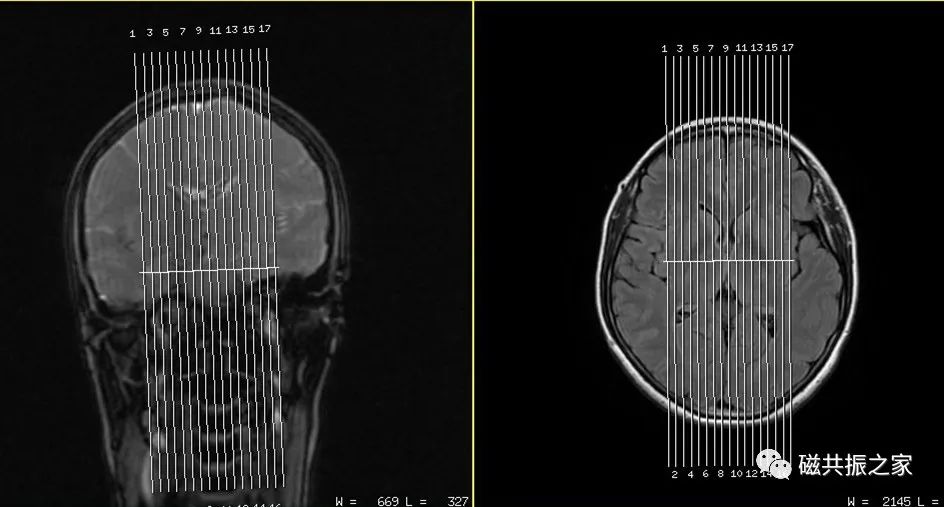

以冠状位和矢状位作为参考定位。在冠状位上定位线平行于两侧颞叶底部的连线;矢状面上平行于前后联合的连线/或胼胝体的前后连线(AC-PC线)/或平行于颅底。扫描范围由后颅窝底到颅顶,合理调整扫描范围,需包括整个病变范围。

7.在实际的临床扫描中如遇到假牙类金属异物无法去除的情况时,可改变成像方位或调整定位线的角度使其尽量避开有干扰的区域。

在实际扫描中改变成像方位或调整定位线的角度使其尽量避开有干扰的区域可有效的改善相应的伪影。